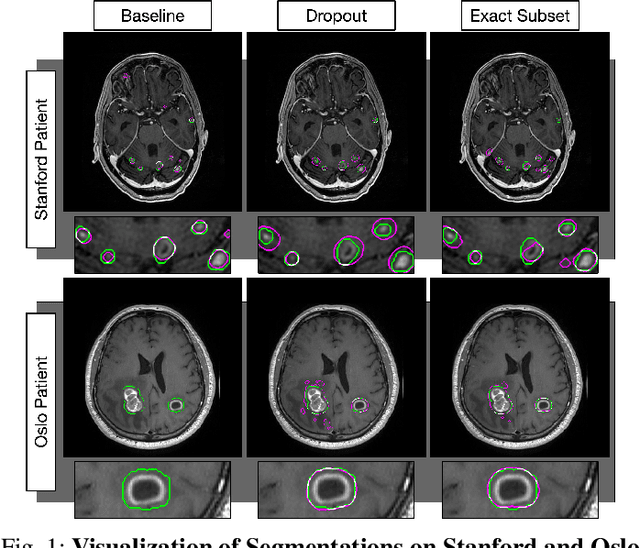

Abstract:The purpose was to assess the clinical value of a novel DropOut model for detecting and segmenting brain metastases, in which a neural network is trained on four distinct MRI sequences using an input dropout layer, thus simulating the scenario of missing MRI data by training on the full set and all possible subsets of the input data. This retrospective, multi-center study, evaluated 165 patients with brain metastases. A deep learning based segmentation model for automatic segmentation of brain metastases, named DropOut, was trained on multi-sequence MRI from 100 patients, and validated/tested on 10/55 patients. The segmentation results were compared with the performance of a state-of-the-art DeepLabV3 model. The MR sequences in the training set included pre- and post-gadolinium (Gd) T1-weighted 3D fast spin echo, post-Gd T1-weighted inversion recovery (IR) prepped fast spoiled gradient echo, and 3D fluid attenuated inversion recovery (FLAIR), whereas the test set did not include the IR prepped image-series. The ground truth were established by experienced neuroradiologists. The results were evaluated using precision, recall, Dice score, and receiver operating characteristics (ROC) curve statistics, while the Wilcoxon rank sum test was used to compare the performance of the two neural networks. The area under the ROC curve (AUC), averaged across all test cases, was 0.989+-0.029 for the DropOut model and 0.989+-0.023 for the DeepLabV3 model (p=0.62). The DropOut model showed a significantly higher Dice score compared to the DeepLabV3 model (0.795+-0.105 vs. 0.774+-0.104, p=0.017), and a significantly lower average false positive rate of 3.6/patient vs. 7.0/patient (p<0.001) using a 10mm3 lesion-size limit. The DropOut model may facilitate accurate detection and segmentation of brain metastases on a multi-center basis, even when the test cohort is missing MRI input data.

Abstract:Magnetic resonance (MR) imaging is an essential diagnostic tool in clinical medicine. Recently, a variety of deep learning methods have been applied to segmentation tasks in medical images, with promising results for computer-aided diagnosis. For MR images, effectively integrating different pulse sequences is important to optimize performance. However, the best way to integrate different pulse sequences remains unclear. In this study, we evaluate multiple architectural features and characterize their effects in the task of metastasis segmentation. Specifically, we consider (1) different pulse sequence integration schemas, (2) different modes of weight sharing for parallel network branches, and (3) a new approach for enabling robustness to missing pulse sequences. We find that levels of integration and modes of weight sharing that favor low variance work best in our regime of small data (n = 100). By adding an input-level dropout layer, we could preserve the overall performance of these networks while allowing for inference on inputs with missing pulse sequence. We illustrate not only the generalizability of the network but also the utility of this robustness when applying the trained model to data from a different center, which does not use the same pulse sequences. Finally, we apply network visualization methods to better understand which input features are most important for network performance. Together, these results provide a framework for building networks with enhanced robustness to missing data while maintaining comparable performance in medical imaging applications.